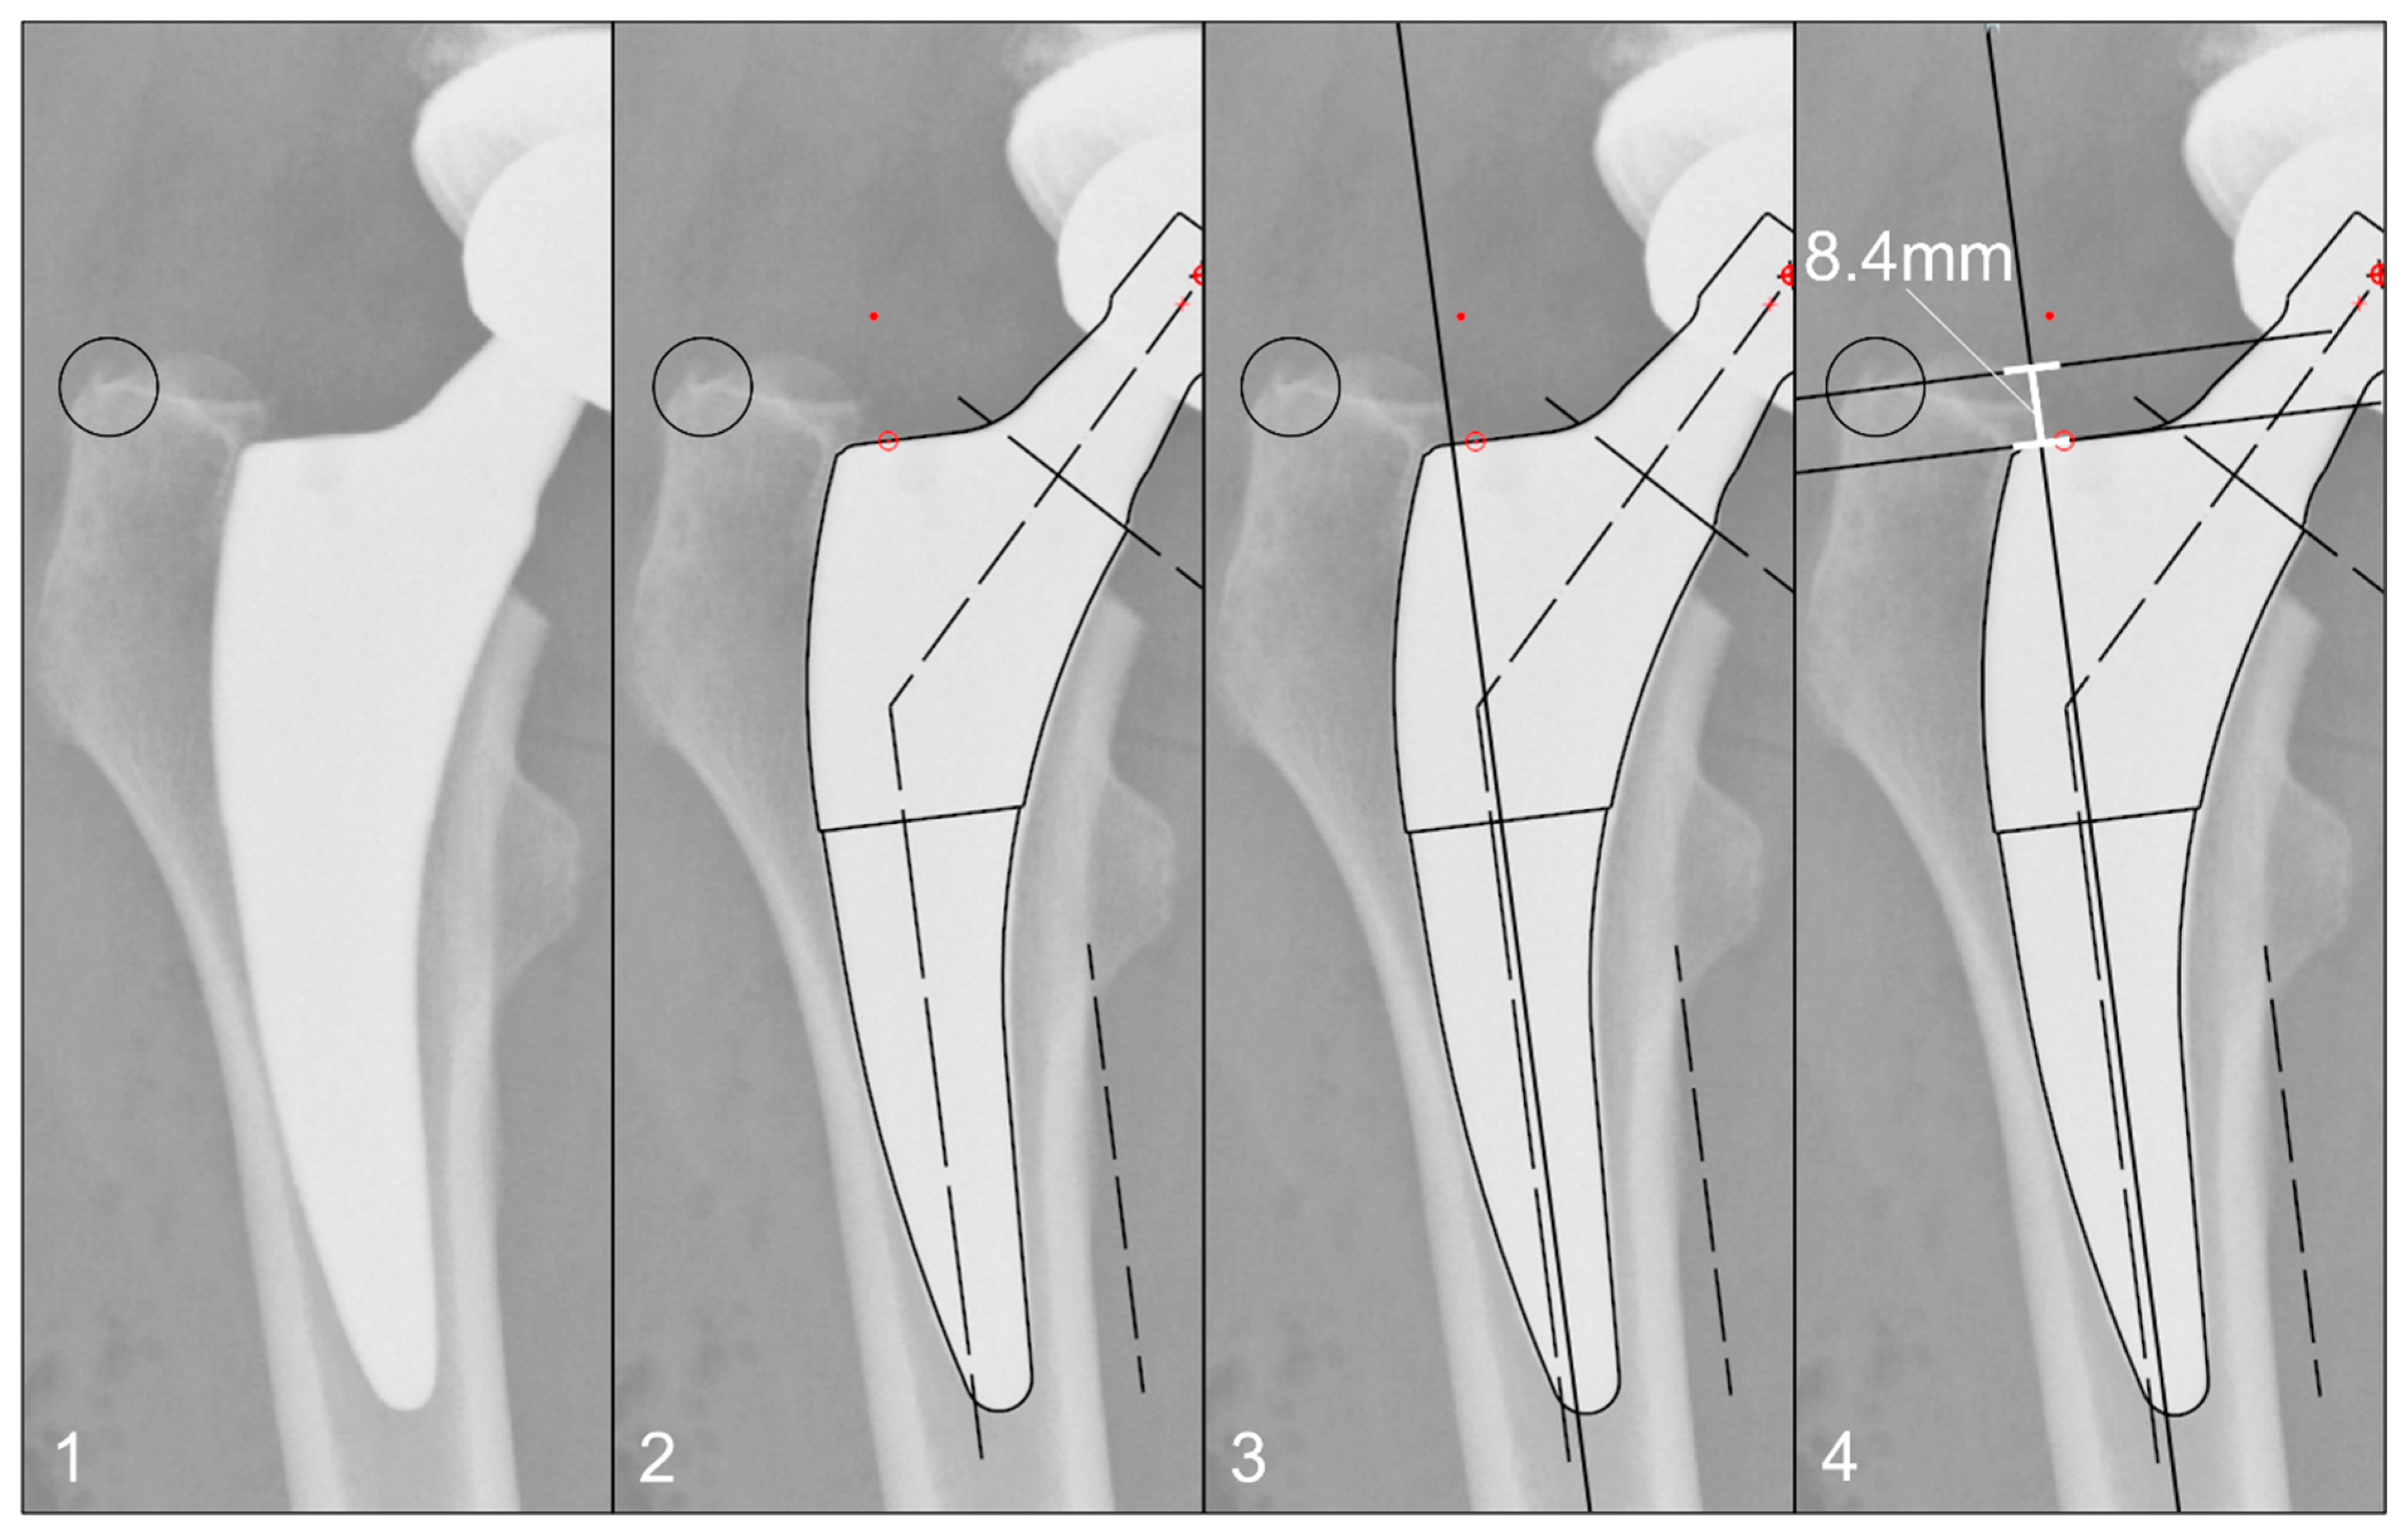

The radiographs were analysed with TraumaCad® software (Brainlab AG, Munich, Germany). We used only standardised deep-centered anteroposterior X-rays of the pelvis, with the central beam perpendicular to the midline and centered over the symphysis, and the legs positioned in 15° of internal rotation with the patient in the supine position. The images were calibrated by measuring the length of the depicted stem from its shoulder to its tip and equating it with the corresponding planning template. In this way, we could avoid any possible errors in our established calibration method with a reference sphere, which can be placed too far away from the central beam or too far away from the film. The measurements of the stem position were subsequently taken on the same axis to neutralise distortions caused by varying flexion and rotation positions of the leg during radiography (Figure 2). The varus/valgus alignment of the stems was determined by measuring the angle between the longitudinal axis of the stem and the longitudinal axis of the femoral canal (Figure 3). Subsidence was determined by measuring the distance from the shoulder of the stem to a clearly definable point at the greater trochanter in the previously determined longitudinal axis of the stem (Figure 4). Due to possible osseous changes over time, such as enthesiopathies or ossifications at the tip of the greater trochanter, defining this point was crucial to measure the correct distance.

Figure 4. Method for measuring the stem position: (1) Identification of a clearly definable point on the greater trochanter, which appears identically on all radiographs up to 10 years postoperatively. (2) Calibration of the image using a planning template, as shown in Figure 2. (3) Determination of the femoral longitudinal axis. (4) Distance measurement of the defined point to the prosthetic shoulder along the femoral longitudinal axis.